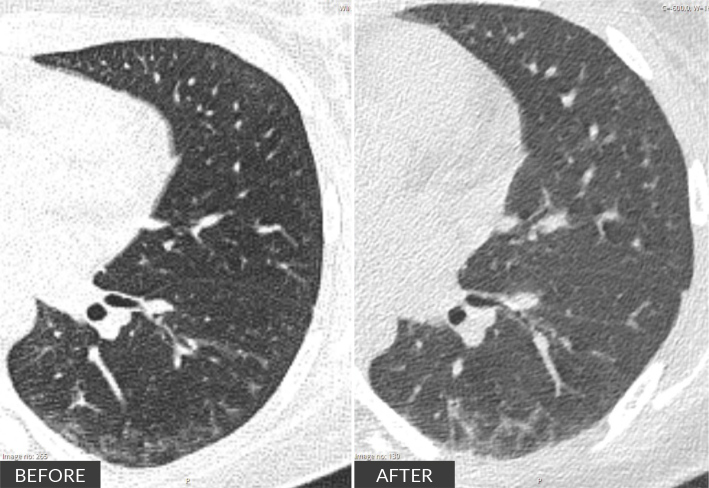

Scleromyositis (SM) is an emerging, distinct entity within the spectrum of diffuse systemic sclerosis (SSc) and autoimmune inflammatory myopathies. It can carry a poorer prognosis due to multisystem involvement and extramuscular complications, with no consensus on treatment strategies currently available. We report on a 20-year-old woman with a history of recurrent infections over the past year, who presented with persistent myalgias for four months. On examination, she exhibited muscle weakness in the scapular and pelvic girdles, along with sclerodactyly. Laboratory results showed elevated creatine kinase (13,000 U/l), aldolase (15.6 U/l), lactate dehydrogenase (1,481 U/l) and myoglobin (4,400 ng/ml). Autoimmune screening was positive for antinuclear antibodies, anti-PM-scleroderma (anti-PM-Scl) 75 and 100, and anti-CENP-B antibodies. An MRI of the pelvic girdle indicated acute/subacute myositis, and electromyography revealed both distal and proximal myopathy. Muscle biopsy showed extensive necrosis with minimal inflammatory infiltration. Nailfold capillaroscopy demonstrated an early scleroderma pattern, while CT and spirometry revealed mild interstitial restrictive lung disease. Initial treatment involved intravenous immunoglobulin (IVIG), mycophenolate mofetil (MMF) and prednisolone. This was followed by maintenance therapy with MMF and rituximab (RTX) every six months for the first year. Over six months, the patient showed progressive improvement in muscle strength and normalisation of muscle enzyme levels. In conclusion, SM presents with variable phenotypes, ranging from mild to extensive systemic involvement. This case underscores the importance of individualised patient stratification and highlights the need for structured induction and maintenance therapy due to the disease's extensive activity.